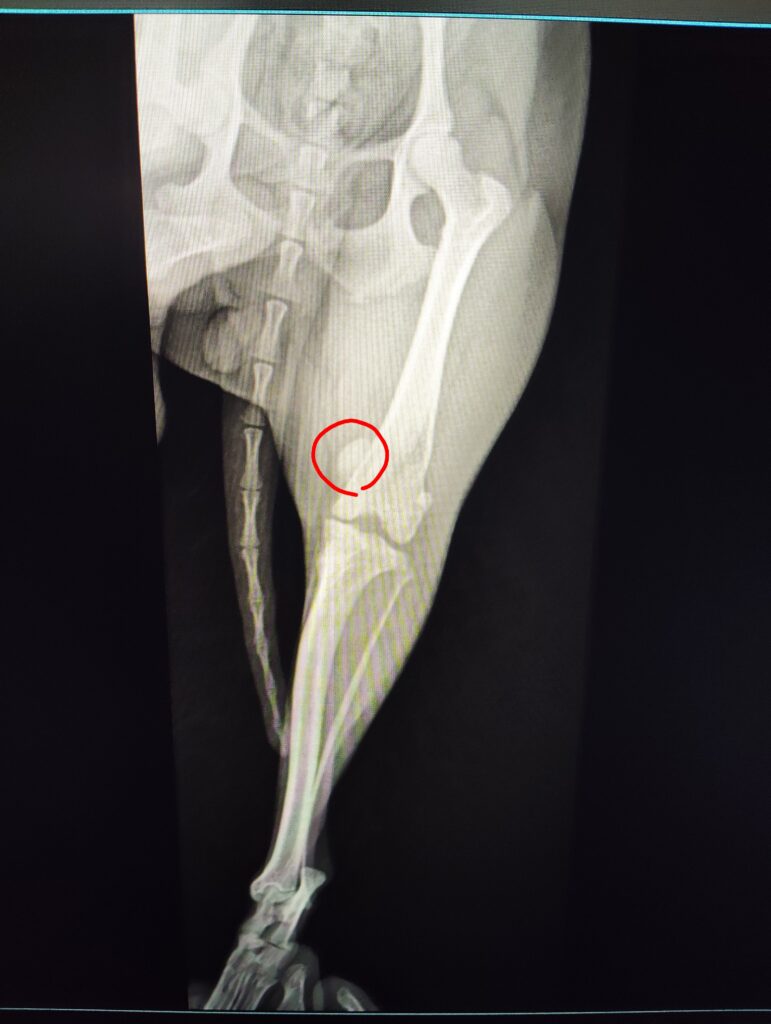

【レントゲン検査】

・左膝蓋骨内方に偏位